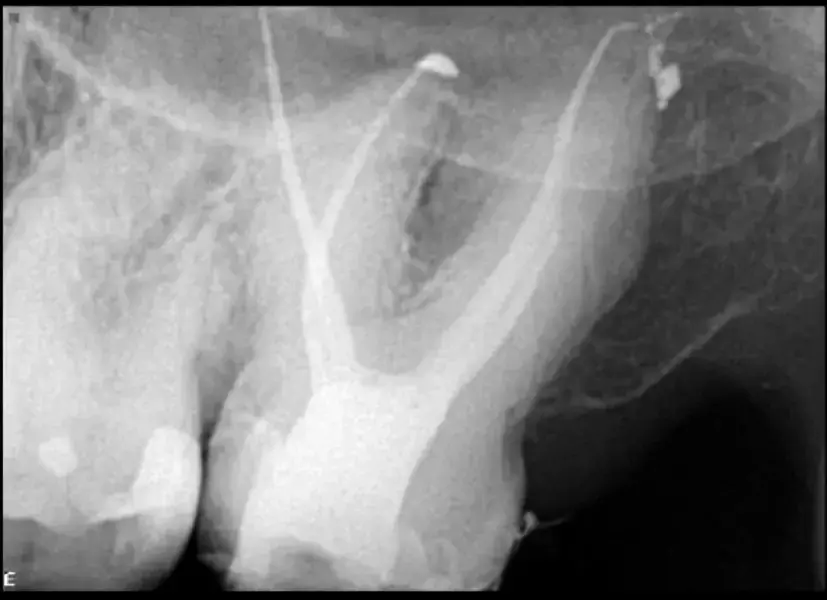

Пациент постъпва по спешност поради остра болка във втори горен молар. Това беше потвърдено при клиничния преглед. Направена е стандартна рентгенография (фиг. 1), която показва много сложна анатомия и калцирана пулпна камера. Историята на този зъб по думите на пациента е, че на него е бил поставен инлей, известно време след което се е появил дискомфорт, който е продължил няколко години без лечение. При контролния преглед му е било казано, че всичко е наред.

Фиг. 1 Предоперативна рентгенография, показваща много сложна кореноканална система и калцирана пулпна камера.